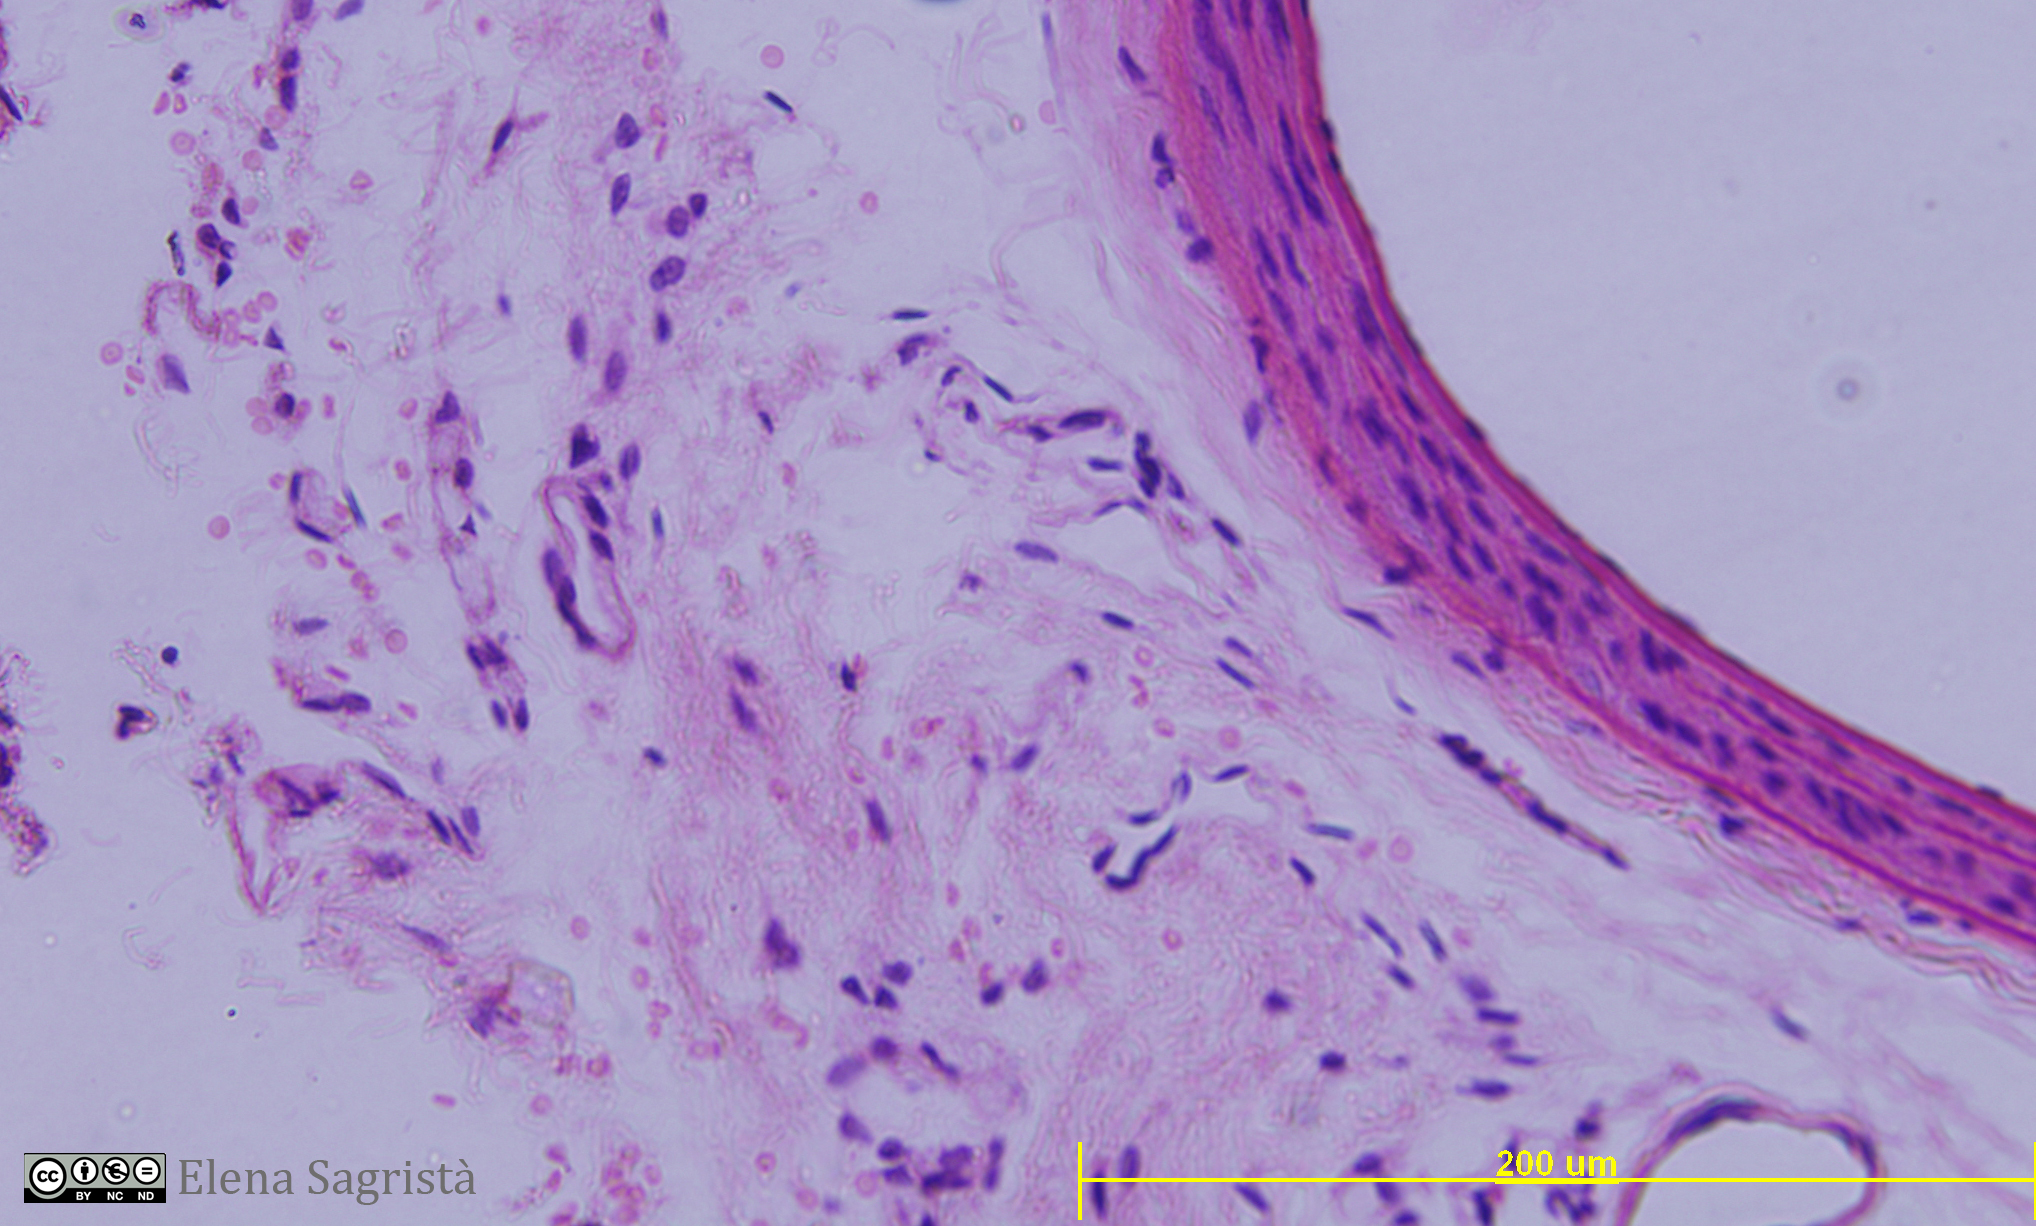

Histologia imatges: 01 Teixit epitelial

Imatges de preparacions histològiques de teixit epitelial. Microscopia òptica.